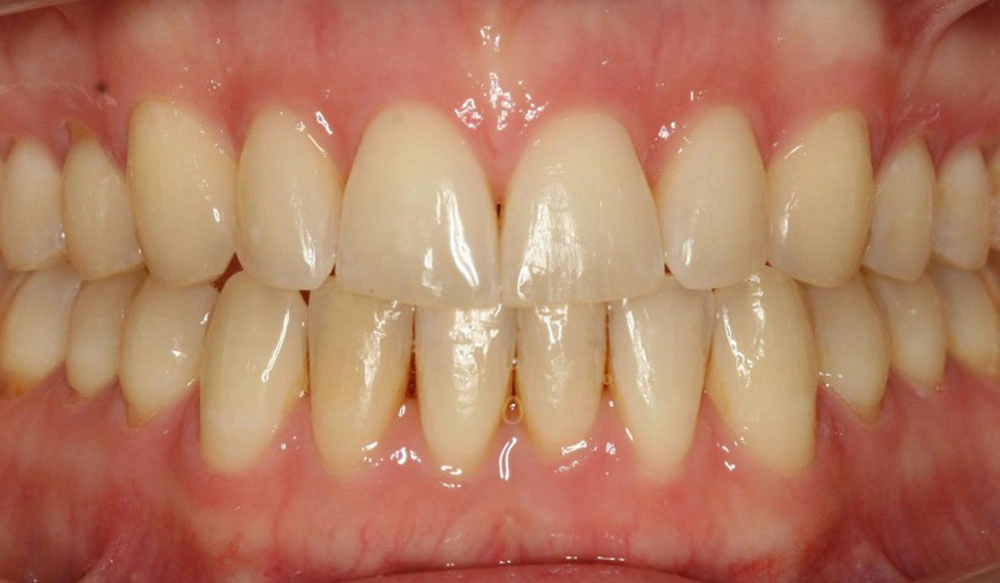

Chen chúc

Chen chúc là tình trạng có sự chênh lệch giữa kích thước răng và không gian có sẵn để sắp xếp răng trên cung răng.

Thông tin bệnh nhân:

Tuổi: 17

Giới tính: nữ

Lựa chọn điều trị Invisalign: Invisalign Comprehensive

Tổng thời gian điều trị:

29 tháng